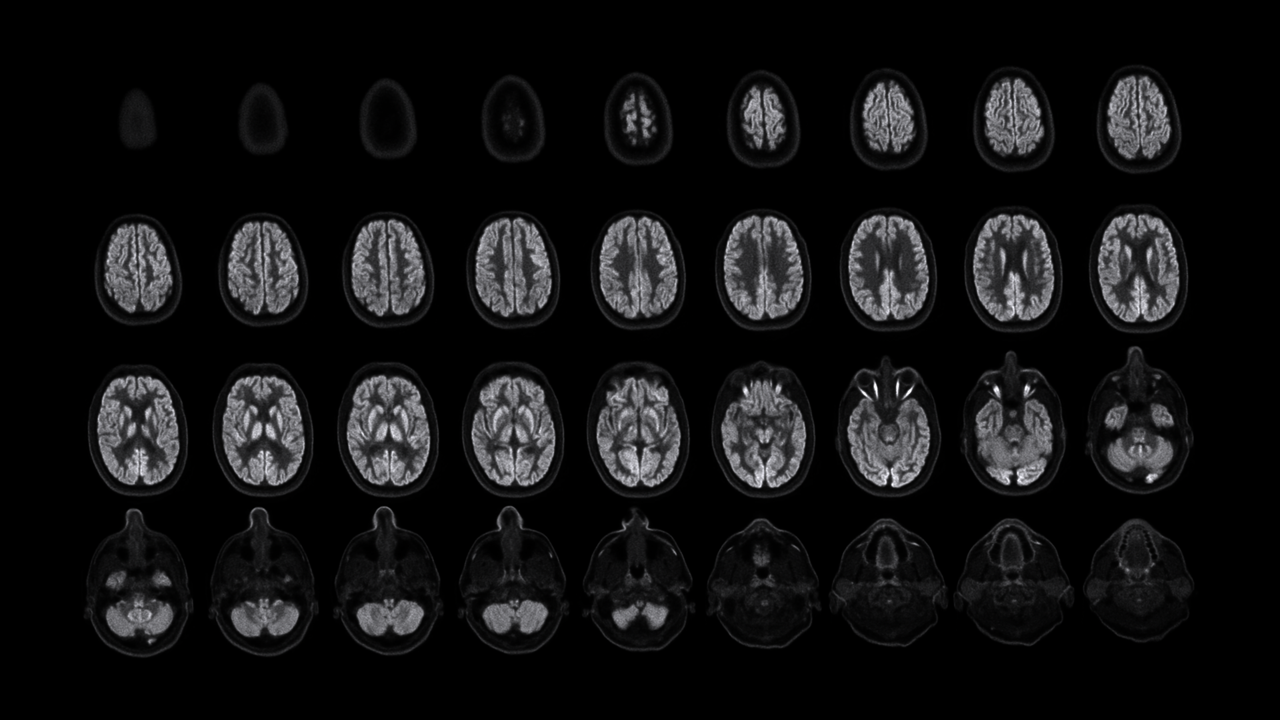

Richard Carson教授与NeuroExplorer (NX)

NX正式进驻耶鲁的时间正是2023年的父亲节,Carson教授亲切地称这台下一代高分辨率脑PET系统为“宝贝”,并称这是最好的父亲节礼物。在展示这份”礼物“之前,Carson教授拿出由第一代PET得到的脑部影像。彼时,每一张图像要花至少10分钟才能获取,且由于图像的质量和分辨率极低,几乎很难识别出那是一张脑部图像。 人类对脑部的探索从未停步,对看到其细微末节的需求亦不止。

NeuroExplorer拥有基于NEMA NU 2-2018标准的超高灵敏度:46cps/kBq,同时配备着先进的时间飞行技术,进一步增强了NX的综合性能。

小型探测器元件确保最精微的结构能被检测,甚至探查特定脑核中的神经递质运动。搭载1.5mm的有效空间分辨率,带来前所未见的解剖细节。